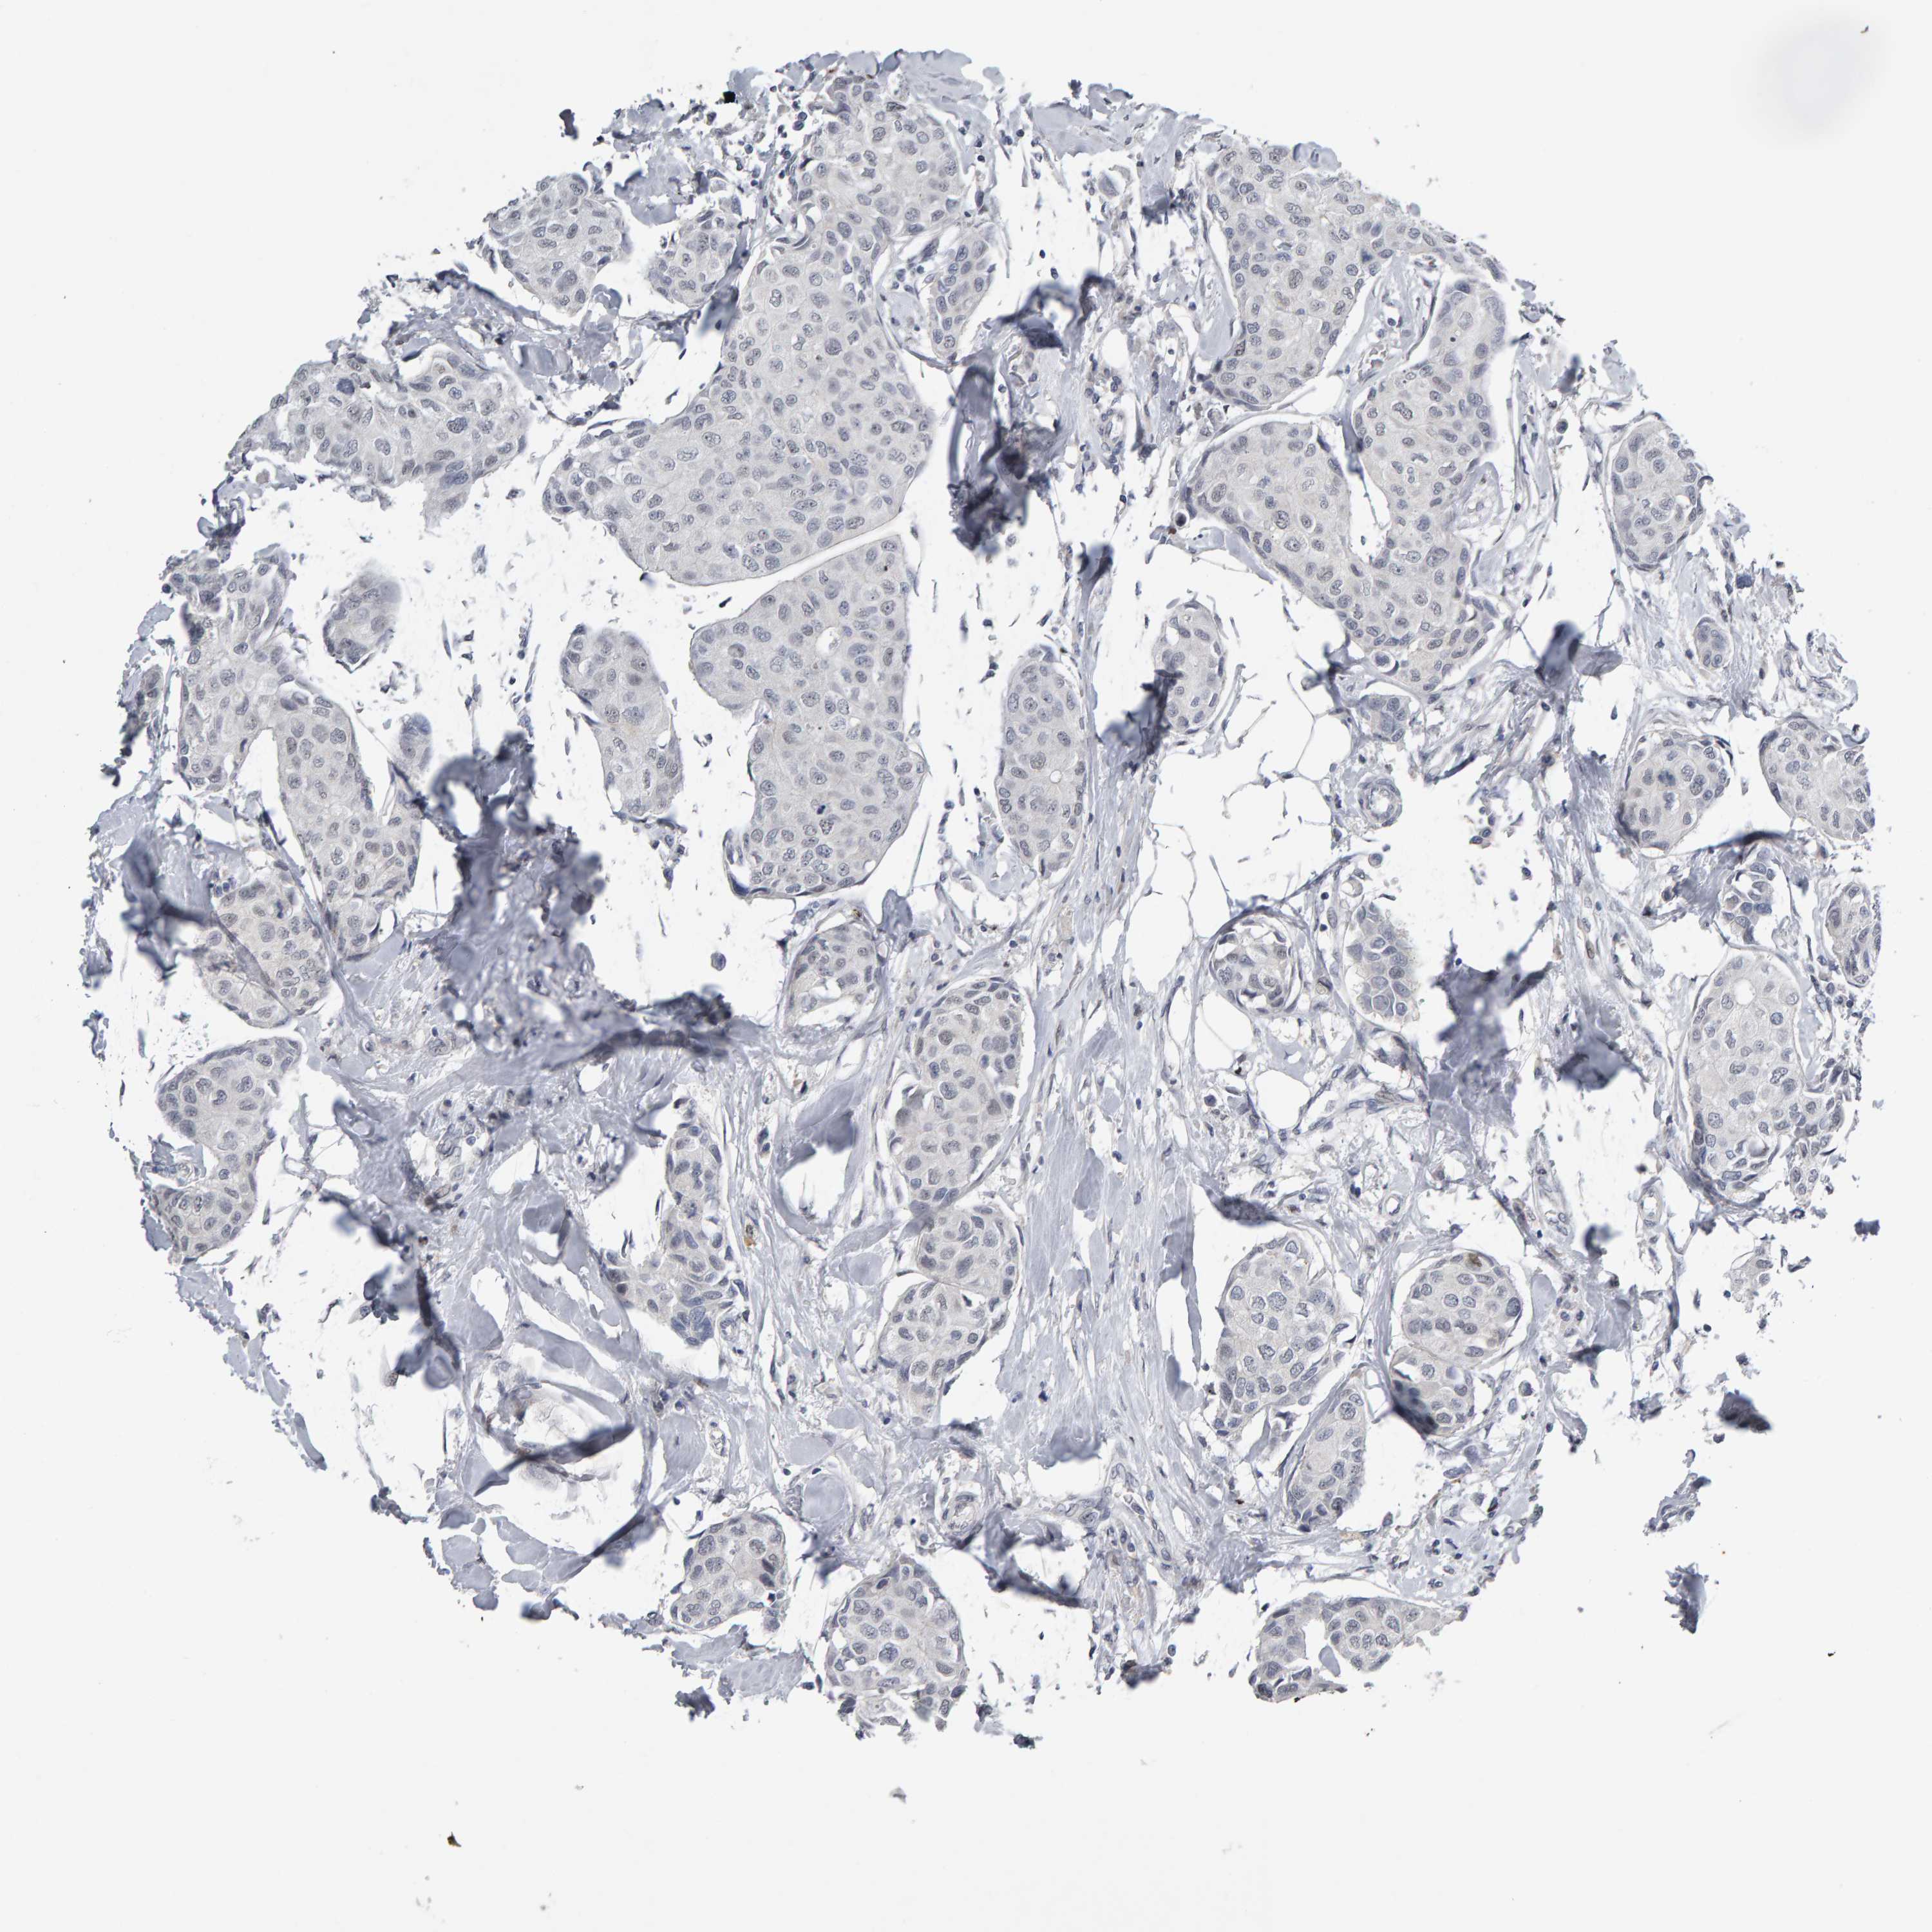

CANCER BREAST CANCER Show tissue menu

BRCA TCGA BRCA VALIDATION PROTEIN EXPRESSION